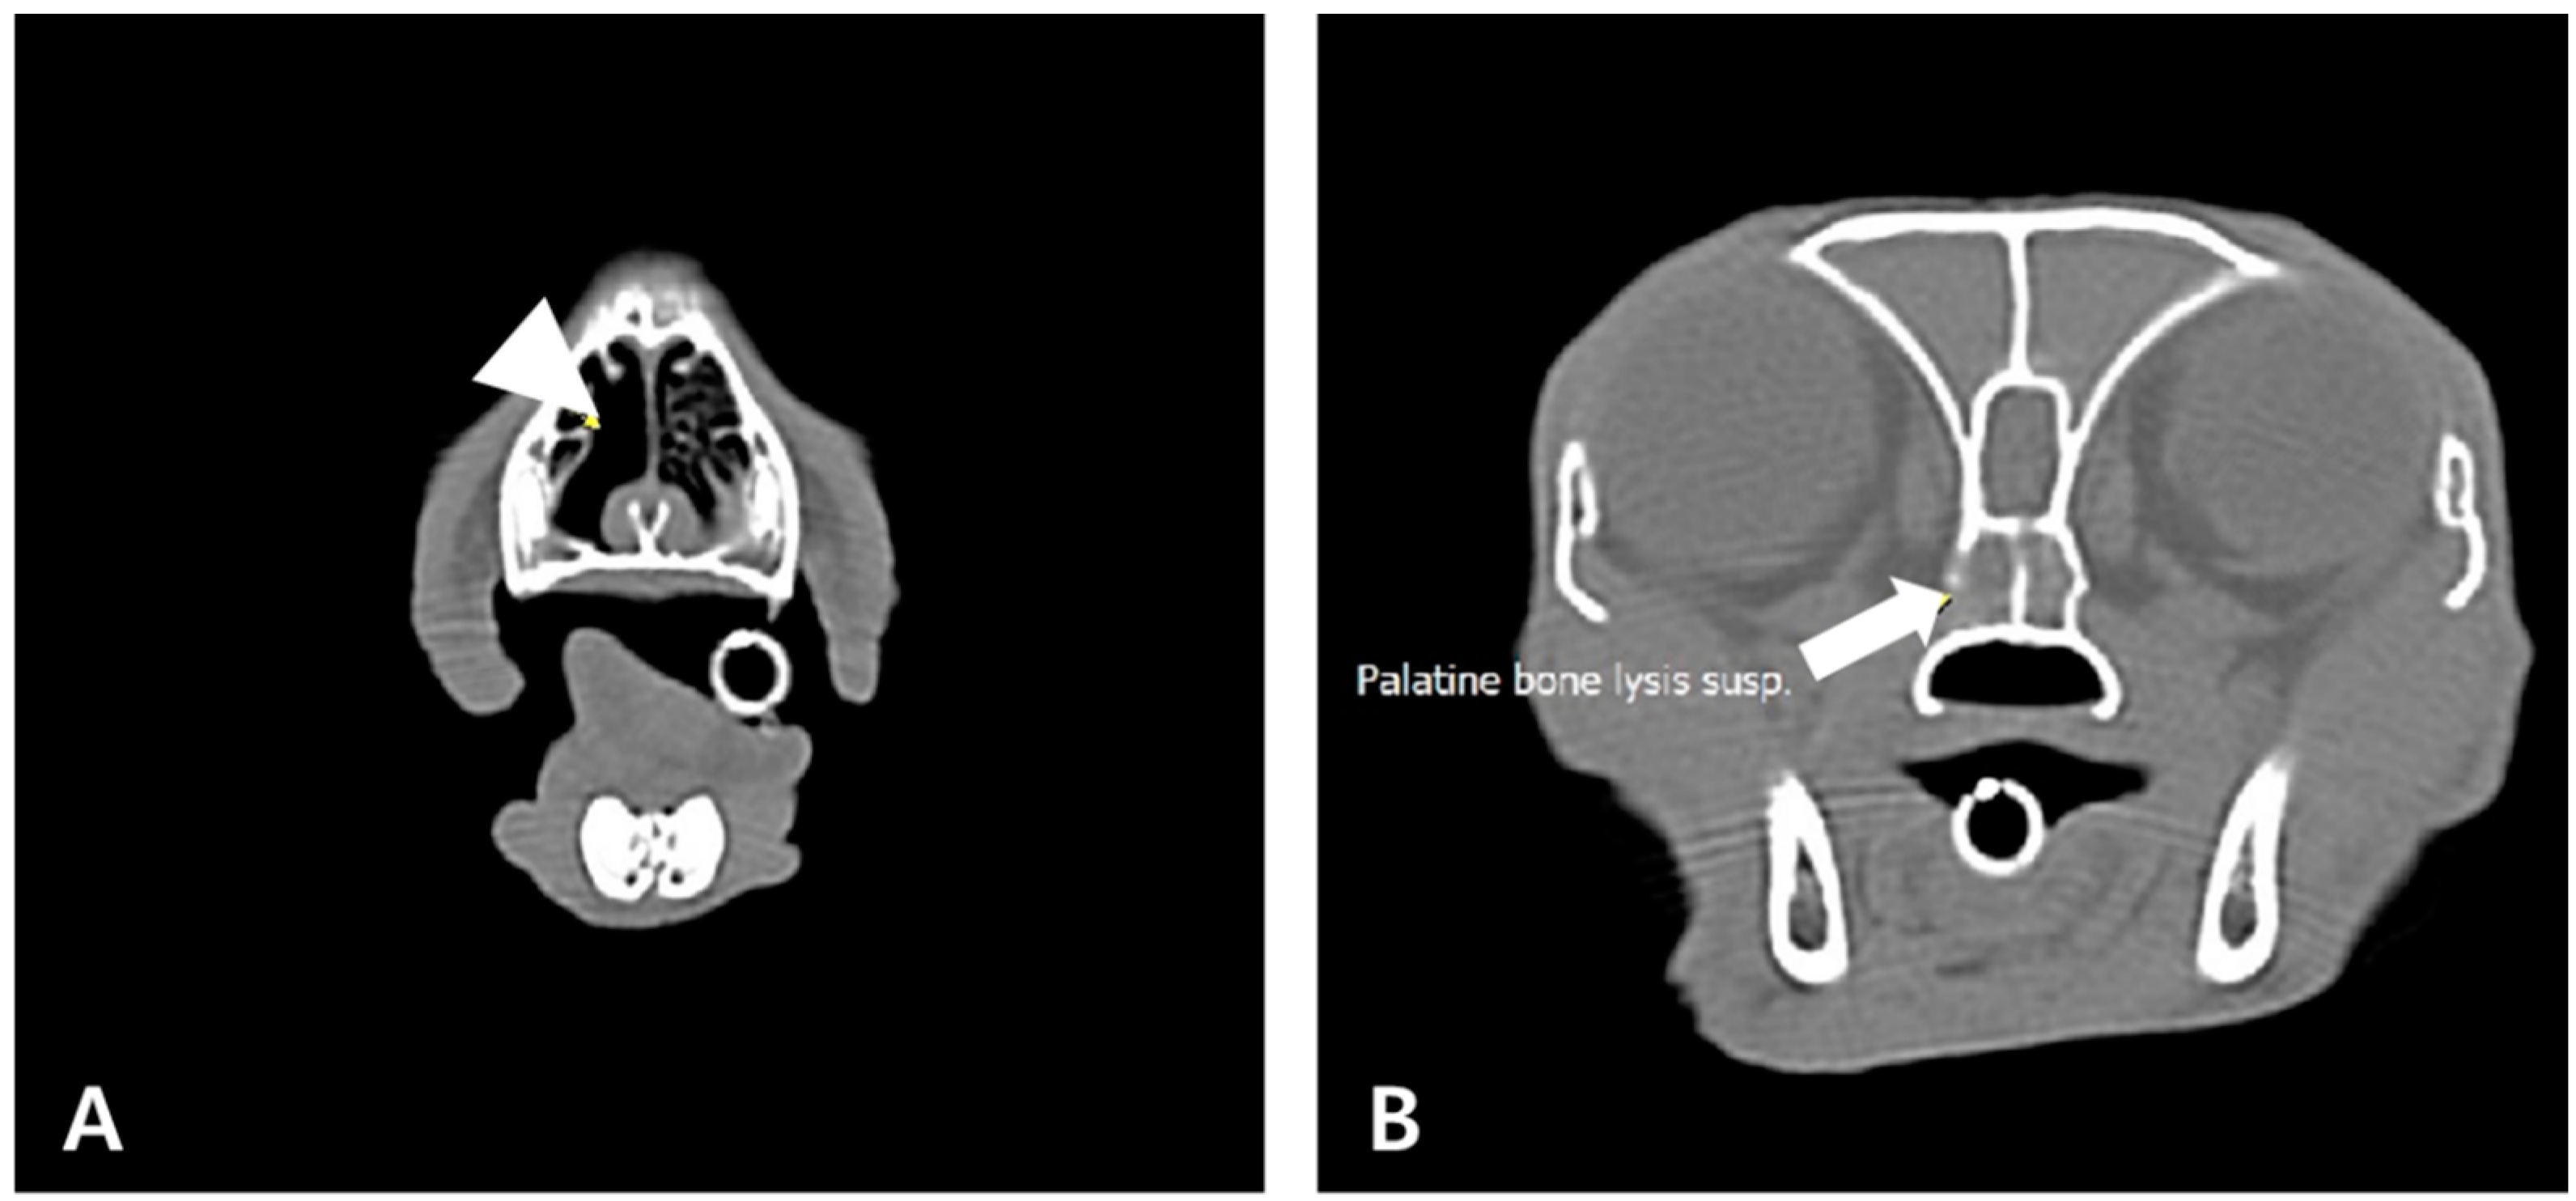

2. Case Description